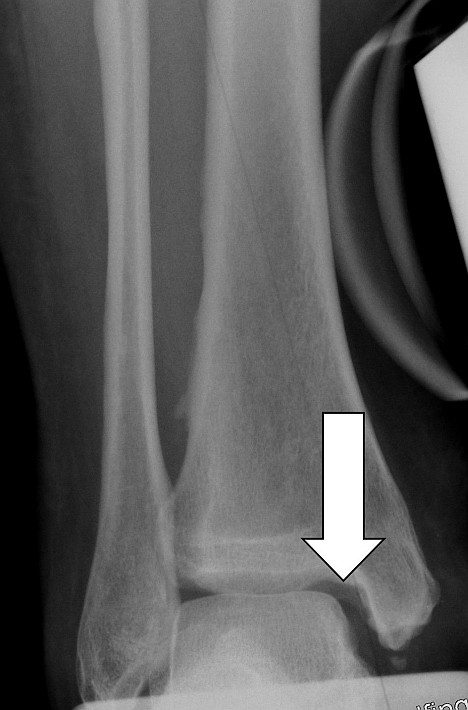

Im Röntgenbild ist die Knorpelschicht nur indirekt durch den Abstand der Knochen im Gelenk sichtbar. Sie bildet den sogenannten Gelenkspalt. Ist diese Schicht noch ausgeprägt, halten die Gelenkpartner im Sprunggelenk einen im Röntgenbild deutlich sichtbaren Abstand zueinander.

Schwindet der Gelenkspalt durch Knorpelabrieb und Arthrose, resultiert eine erhöhte Belastung des angrenzenden Knochens. Die Folge ist vermehrter Knorpelabrieb.

Wie erkennt der Arzt die Sprunggelenksarthrose im Röntgenbild?

Eine Verschmälerung des Gelenkspaltes im Sprunggelenk weist indirekt auf eine Knorpelschädigung hin und ist damit ein frühes Zeichen der Sprunggelenksarthrose. Resultierend aus dem Knorpelschaden kommt es zu einer Anpassungsreaktion des umliegenden Knochens. Eine Verdichtung des Knochens (Sklerosierung) am Sprunggelenk ist die Folge des Knorpelabbaus.

Zeichen einer fortgeschrittenen Sprunggelenksarthrose im Röntgenbild

Der Gelenkspalt des Sprunggelenkes verschwindet zunehmend und der gelenknahe Knochen verdichtet sich immer stärker. Durch die vermehrte Belastung reagiert der Knochen im Randbereich mit der Ausbildung von Knochenanbauten (sog. Osteophyten). Die Druckzunahme im Knochen kann im Verlauf zu blasenförmigen Knochenauflösungen (sog. Geröllzysten oder Geoden) führen. Dies sind Hohlräume im Knochen, die durch Knochentod (Osteonekrose) entstehen. Als letztes Zeichen einer Sprunggelenksarthrose verformen sich die Gelenkpartner, weil die Belastungslinien des Gelenkes sich verändern.

Am oberen Sprunggelenk flacht das Sprungbein (Talus) häufig ab und der Knochen gleitet nach vorne. Durch diese Veränderungen resultieren zunehmende Einschränkungen, die sich weiterhin auf die benachbarten Gelenke auswirken können.